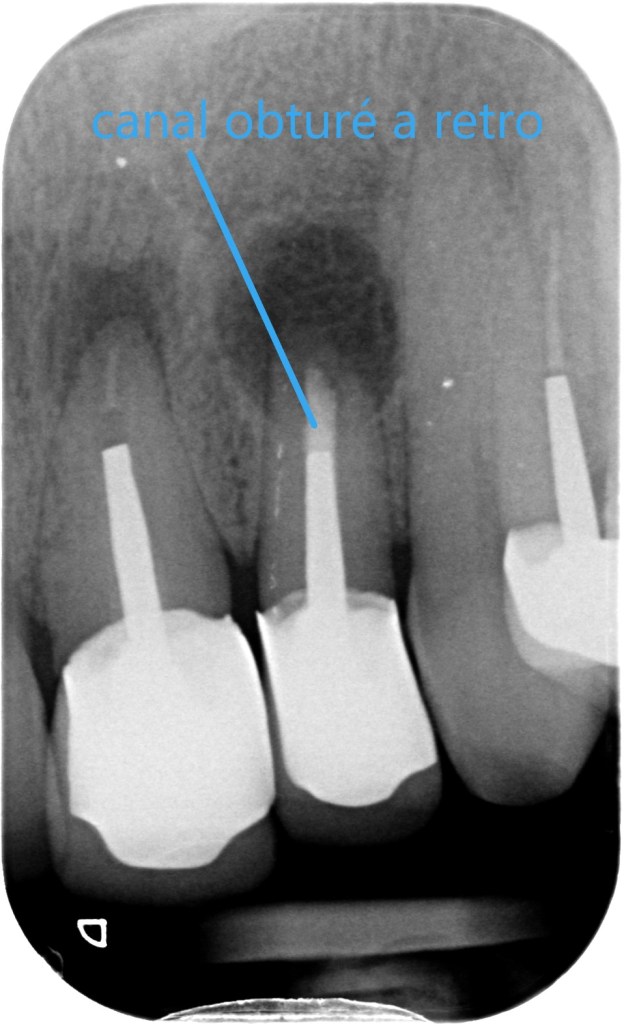

radio post-opératoire (ré-obturation a retro du canal)

• Le canal de la dent est nettoyé sur quelques millimètres, désinfecté, puis obturé a retro.